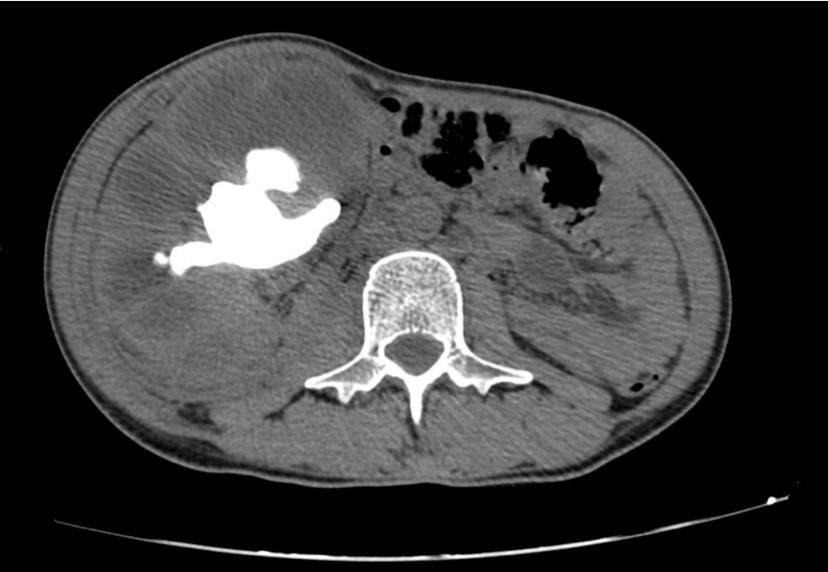

Renal Trauma

Renal trauma accounts for approximately 1-5% of all trauma admissions and as many as 10% of patients who sustain abdominal trauma. Injuries can range from contusions to life threatening injury. The types of trauma include penetrating (gsw, knife), blunt force (mva, sports injury), post procedure etc..

Patients may have abdominal/flank pain on the affected side, hematuria may also be present.